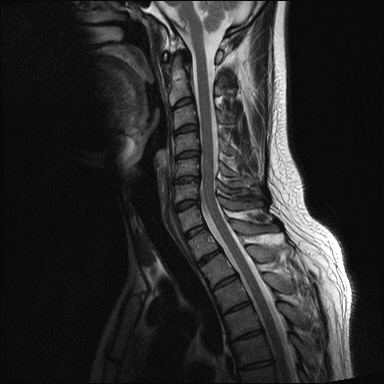

ȸ ϸ鼭 ۼ Դϴ. Ű 172 72 35 ˰Ե ͳ õ ijħ ǥغ ϱ ȣϽ 1C.ڵӸ 1C.ٸǷ 1C.ټ Ǹ 1C.ٱ () 1C.߷ () 1C.Ƿ () 2C.ھȱ, 2C.ڴ 2C.ھ˷⼺(˷) ḷ 2C.ٴ, 2C.ٰḷ 2C., 2C.ٺ, 2C.ٸ 2C.پ˷⼺(˷) 3C.ġ Ű 3C. 4C. 6C.ڸ 6C.ھ Ḳ 6C.ڻ 1T.ȣ 4T. 3T.ȯ, 5T.ȯ ҷ, 6T.ټ 6T.ٽƮ 9T.˷ 10T.ٸǷ 2L. 㰡 2L.ȣ 3L. 3L.ڹ 4L.° 4L.ھƷ 4L.ڿ, 4L.ڵ Ʒ 5L.ڴٸ Ʒκ̳ 5L.ڹ߸̳ õ().¦ٸ ()ũ( ߰Ż) Ը Ͽ ũ(߰Ż), ũ(߰Ż)ġ, , Ḳ , , Ḳ ġ ȱ ǰϰų ڸ, , ڰ , , Ǵ ġ ô ¦ٸ(ٸ̰ ٸ) , 㸮 ̳ ġ Ƹ ġ ħ ߷, , нɷ 帶, ɱٰ, ɺ ڸǥغ ǥغ ϰ ߴ ġ 1. ũ 1) ߺñ: 1 Ӹ ־ ʹ 2)˻ : ** x-ray MRI Ȯ 3,4,5 ũ ̸, Ư 4 ũ ¦ Ƣ . 3)ġ: Ű漺 , ġḦ ʾҰ, Ư ǿ ħ °, Ȱġ(Ȳ,ħ, ȸ ) . 4)ġ : 1.Ͻ ȿ ־, ð 2. 㸮() 1) ߺñ: 3 ϱ ٳѱ⸦ ڱ 㸮 , ģ ƮĪ شٸ 㸮 ȭ ƮĪ Ʋ . 2)˻ : ǿ 㸮 ġ . 3)ġ: ħ ȰġḦ 4)ġ :Ͻ ȿ ־ ɰų 㸮 3. ڰ 1) ߺñ: ڰ̰ ִ Ȯ 5 Ǵܵ 2)˻ : 6~7ð 2~3ð ڸ , ȣ 3)ġ: ġḦ ް , ڰ *** ߿ Ƽ ϰ 4)ġ : ڸ 4. 1) ߺñ: 2~3 ְų Ͻ ־ 2)˻ : ˻縦 ʾ, ʰ ô ó 3)ġ: 4)ġ : 5. ô 1) ߺñ: 3 ڿ ɾƼ ٸ µ ٸ ª 2)˻ : 7 Ȱ X-RAY ణ ô ִٰ Ǹ 3)ġ: ġ 4)ġ : Ͻ 6. (˷ ḷ) ȱ 1) ߺ: 5 2)˻ : Ű 3)ġ:1~2 ѹ ް Ⱦ ֱ ְ 4)ġ : , ħħϰų 7. , Ѽ ȣ ߺñ: ɸ Բ ڰⰡ , ڸ, ä, 2)˻ : Ḧ ʾ, ڰ Ⱑ ư, Ѽ Ҵ Ȳ µ ϰ ȸ ȭ ˷ֽ ǥغ ϴ ڸ ϴ. 㿡 ħ ȸԲ ˷ֽ Ư ġü ġὺƮĪ Բ ġ ȭ ʰ ȸǴ ڼ ϴ ϴ. ˷ֽ ͵ ̳ ǰ ͳݿ ִ ٸ Դϴ. ϴ ȭ Ÿϴ. ϴ. پٰ ϴ. ϴ پų ϴ. 30и 30 ̻ ϶ ϼ̽ϴ. 30иٴ ϰ ҷ ߽ϴ. Ȳ ٷ ϴٰ ٽ ϴ. ķ 鵵 Ÿϴ. γ ȸԲ ڵȽϴ. ٽ ȭּż Ȳ ϰ ʰ ּ̰ ڼ ణ ߸ϰ ־ ֽð ʰ ˷ּ̽ϴ. ȭ Ŀ ߰ ȭ ߾ ߴµ ϴٰ 1 ȭ ѹ ʾҾϴ. ˷ֽ ˷ֽ 뿡 ణ ̴ ε ̼ϰ ٸ ̷ Դϴ. ʰ ϴ ڼ ü ٽ ϰ ˷ּ̰ а ߴص ϰ ˷ֽ θ ϶ ϼ̽ϴ. ˷ֽŵ Ȱ ϰ غ ı øڽϴ. ȸ 㵵 ű Դϴ. ۼ ıԴϴ. http://najari.kr/Board/index.php?Code=free1&No=5141&action=View&st=&sn=&sc=&Keyword=&Page=1 |